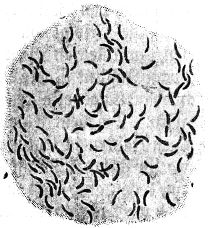

Sehr vieles sprach zugunsten der ersteren Anschauung; vor allem entsprach sie den Erfahrungen, die bei der Erforschung der lebenden Wesen unserer Erde bis dahin gesammelt waren. Der einwandfreie Nachweis ihrer Richtigkeit stieß aber auf eine sehr große Schwierigkeit: fast überall, wo wir in der Natur Bakterien in größeren Mengen begegnen, finden wir verschiedene, ja meist sogar sehr zahlreiche verschiedene Formen in buntem Durcheinander; z. B. treffen wir in einem Tröpfchen Zahnschleim regelmäßig kurze und lange, dünnere und dickere Stäbchen und Schrauben, daneben kleinere und größere[5] Kugelbakterien miteinander vermengt (vgl. Abb. 2). Es war so gut wie unmöglich, an solchen Bakteriengemischen einwandfreie Beobachtungen über die Fortpflanzungsweise der Bakterien zu machen. So ist es verständlich, daß über diese Frage die Ansichten lange Zeit auseinandergingen.

Abb. 2

Abb. 2.

Ausstrichpräparat von menschlichem Zahnschleim, gefärbt, etwa 1000fach vergrößert. Mannigfaltige Bakterien in buntem Gemisch.